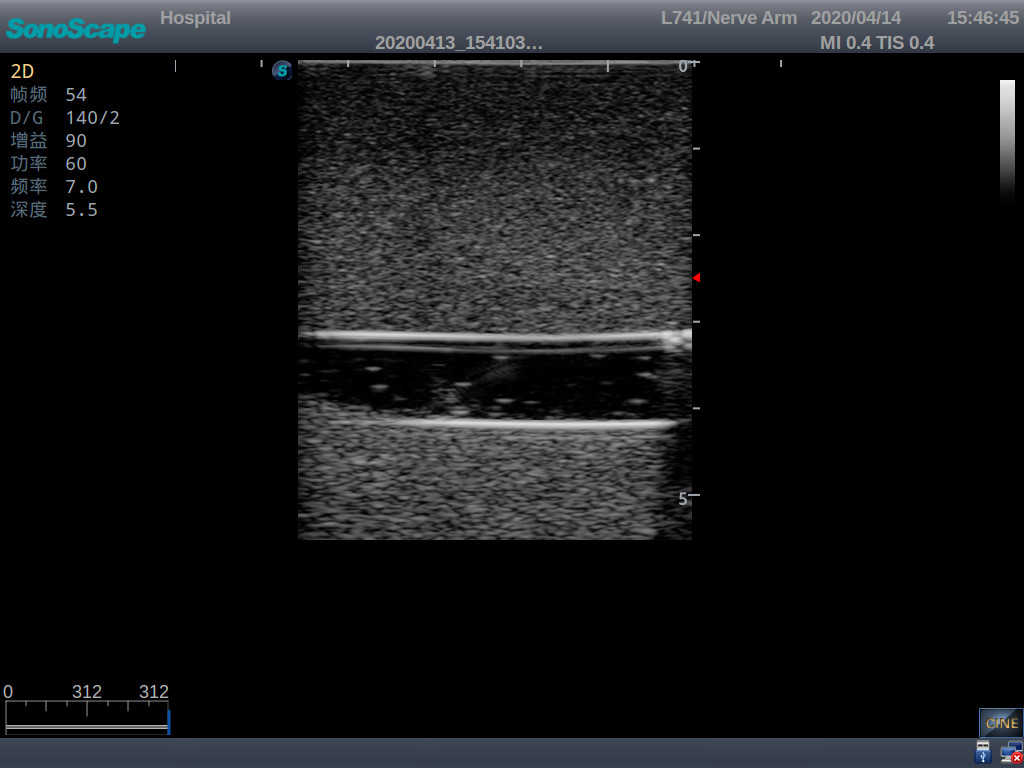

PICC Ultrasound Training Model

Model TYE1510.1

Outline

It is a model covering up from lobulus auriculae plane to the umbilical plane, and it has anatomical structures like clavicle, rib, sternocleidomastoid, jugular vein and basilic vein.

1)   Made of high molecular polymer ultrasound material, close to the real skin

2)   It can be used by real ultrasound machines

3)   Clear and real images of the tissues and organs (basilic vein and superior vena cava)